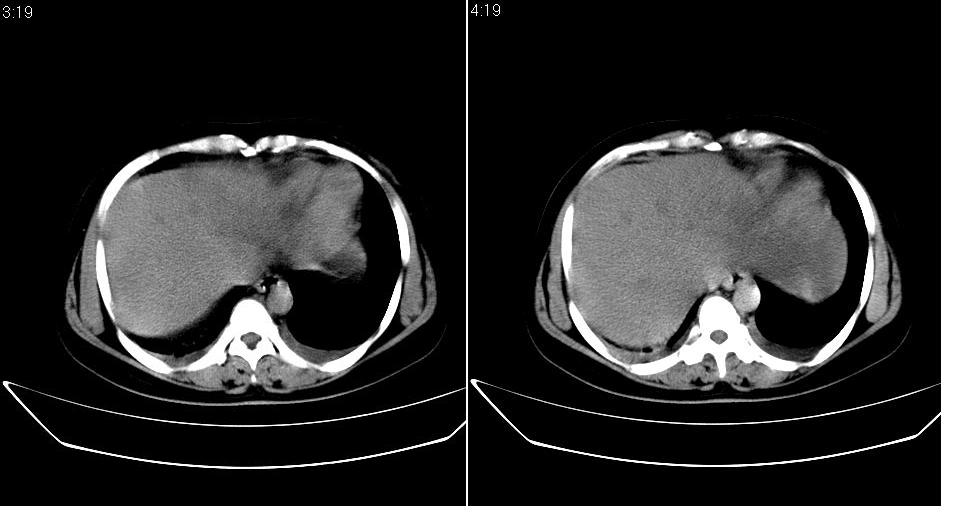

女 36岁,腹痛月余,b超提示肝左叶占位,腹水。

肝脏左叶明显增大,各叶比例失调,左叶实质内不均匀低密度影,似乎有肝内胆管的扩张,没有增强实在不好判断,不知患者肝功能是否正常,我觉得象胆管细胞癌。

1)考虑肝左叶肝癌;建议行进一步检查。2)肝硬化,脾稍大。3)双侧少量胸腔积液。

肝脏左叶明显增大,各叶比例失调,左叶实质内不均匀低密度影,增强!